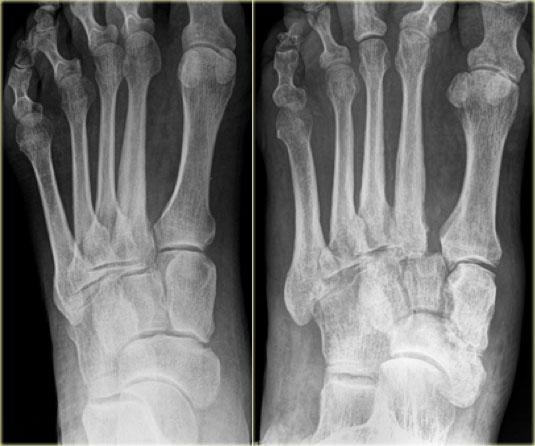

Đây là hình chụp X-quang của một bệnh nhân bị bệnh thần kinh do đái tháo đường và bàn chân đỏ nóng.

Trong giai đoạn cấp tính, hình chụp X-quang có thể bình thường và không thể loại trừ chẩn đoán bệnh xương khớp thần kinh Charcot cấp tính.

Trong vòng 4 tháng có sự giảm dần độ nghiêng xương gót với biến dạng ngựa tại khớp cổ chân.

Có sự phá hủy khớp cổ bàn chân với biến dạng bàn chân đế cong điển hình.

Bony debris is seen on the dorsal aspect of the foot.

Ở ngoài cùng bên trái, hình ảnh X-quang bình thường trong giai đoạn cấp tính của Charcot.

Tiếp theo là hình ảnh bệnh lý thần kinh-xương khớp Charcot tiến triển với trật khớp Lisfranc.